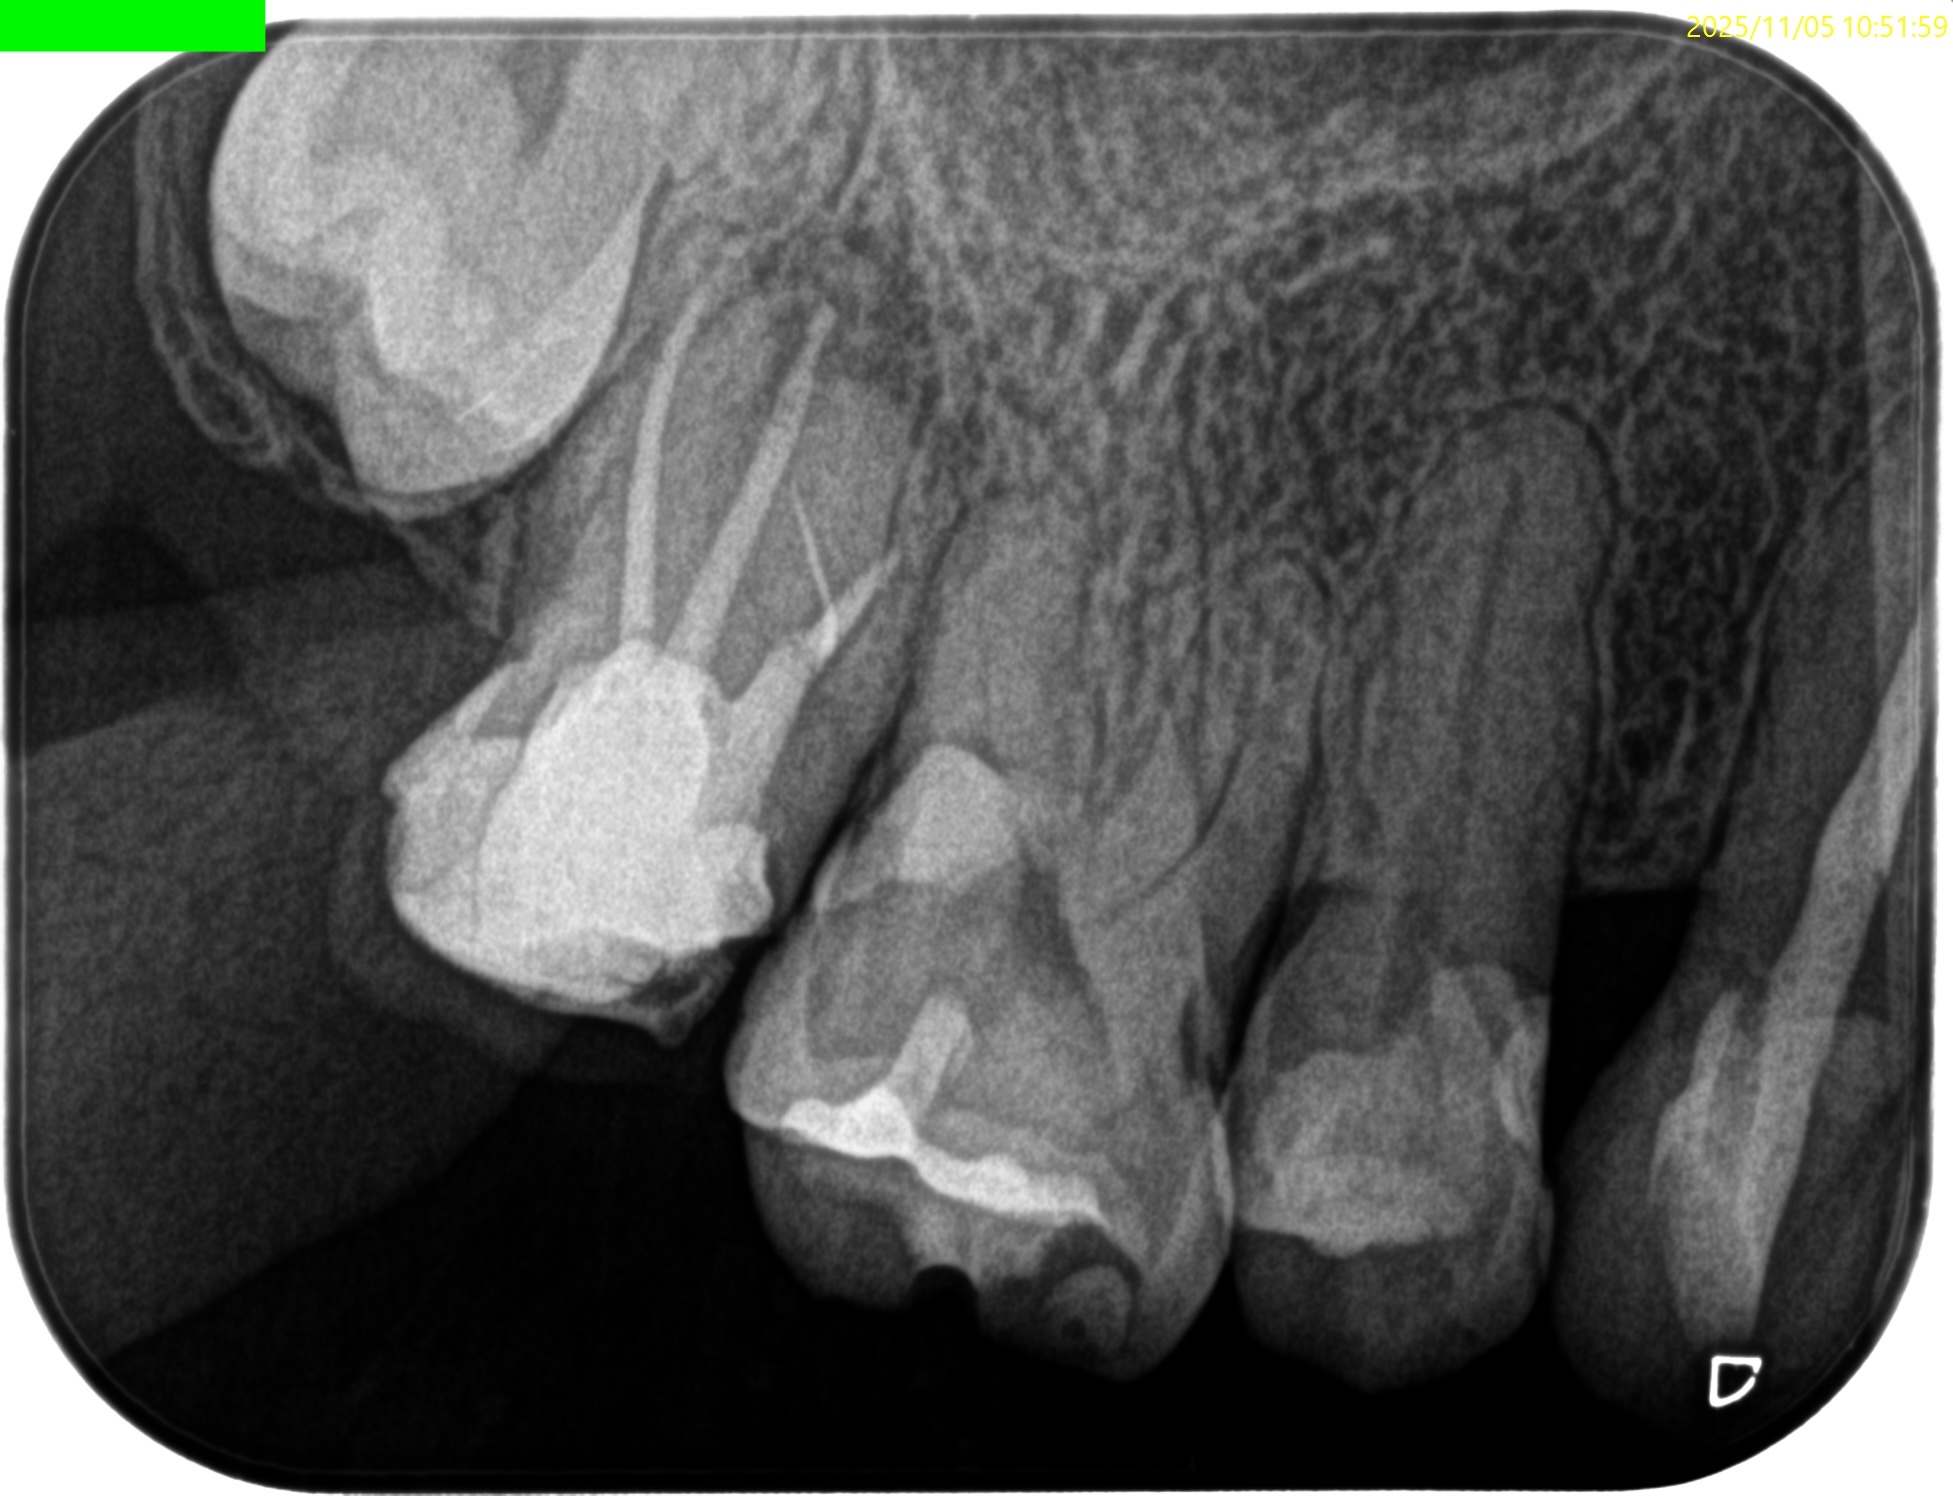

近心根にファイルが折れ込んでいる。

が、

それが問題なのでなく、可及的無菌的な歯内療法がなされていないことの方が問題なのである。

患者さん曰く、

ラバーダムなど見たことも聞いたこともない

だそうだ。

MB

DB

P